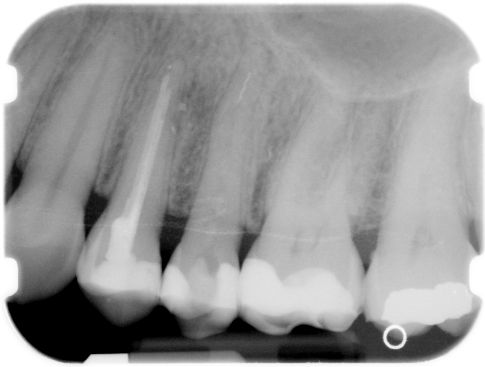

ad b. Een vijl afgebroken halverwege het wortelkanaal.

Het kanaalgedeelte boven de vijl wordt geprepareerd met een

Gates Glidden drill

die afgeslepen is tot zijn breedste punt. Een ronde

LN-boor

met een diameter van 0,8 millimeter kan hier ook goed voor gebruikt worden. Met de behandelmicroscoop is de bovenkant van de afgebroken vijl goed te zien. Nu wordt met speciale ultrasone tips weer enkele millimeters van de vijl iets vrij geprepareerd. De ultrasone trilling helpt mee de vijl los te maken. Blijft de vijl nog vastzitten dan kan met het IRS-systeem geprobeerd worden de vijl vast te klemmen en er uit te trekken. Lukt dit nog niet dan opnieuw enkele millimeters verder langs de vijl vrij preparen.